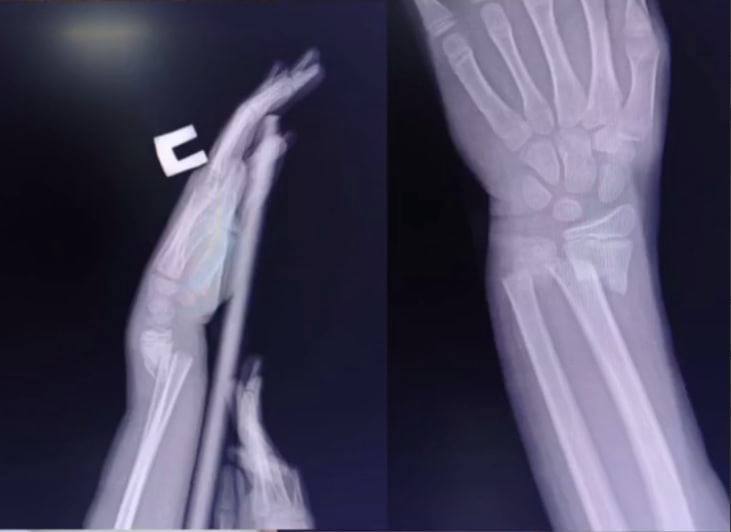

В прошлом месяце травмировался другой ребёнок в штате Алабама. Женщина по имени Тери Уиммер в запрещённой соцсети сообщила о том, что ее сын Паркер невольно стал участником пранка, в результате чего сломал запястье в двух местах. Школьнику потребуется хирургическое вмешательство.

По словам тёти одного из пострадавших, после розыгрыша племянник получил двойной перелом руки со смещением.